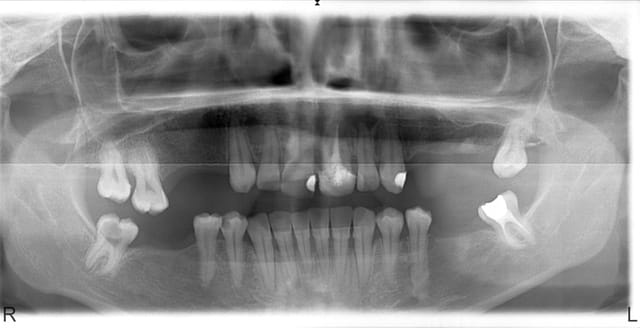

Finalement patiente revenue 8 ans plus tard et finalisée par endos, paro stellites...

Désolé je n'ai pas de belles photos de greffes osseuses comme D57 ou mes collègues implanto...

(la 22 est quasi cicatrisée pour les observateurs)